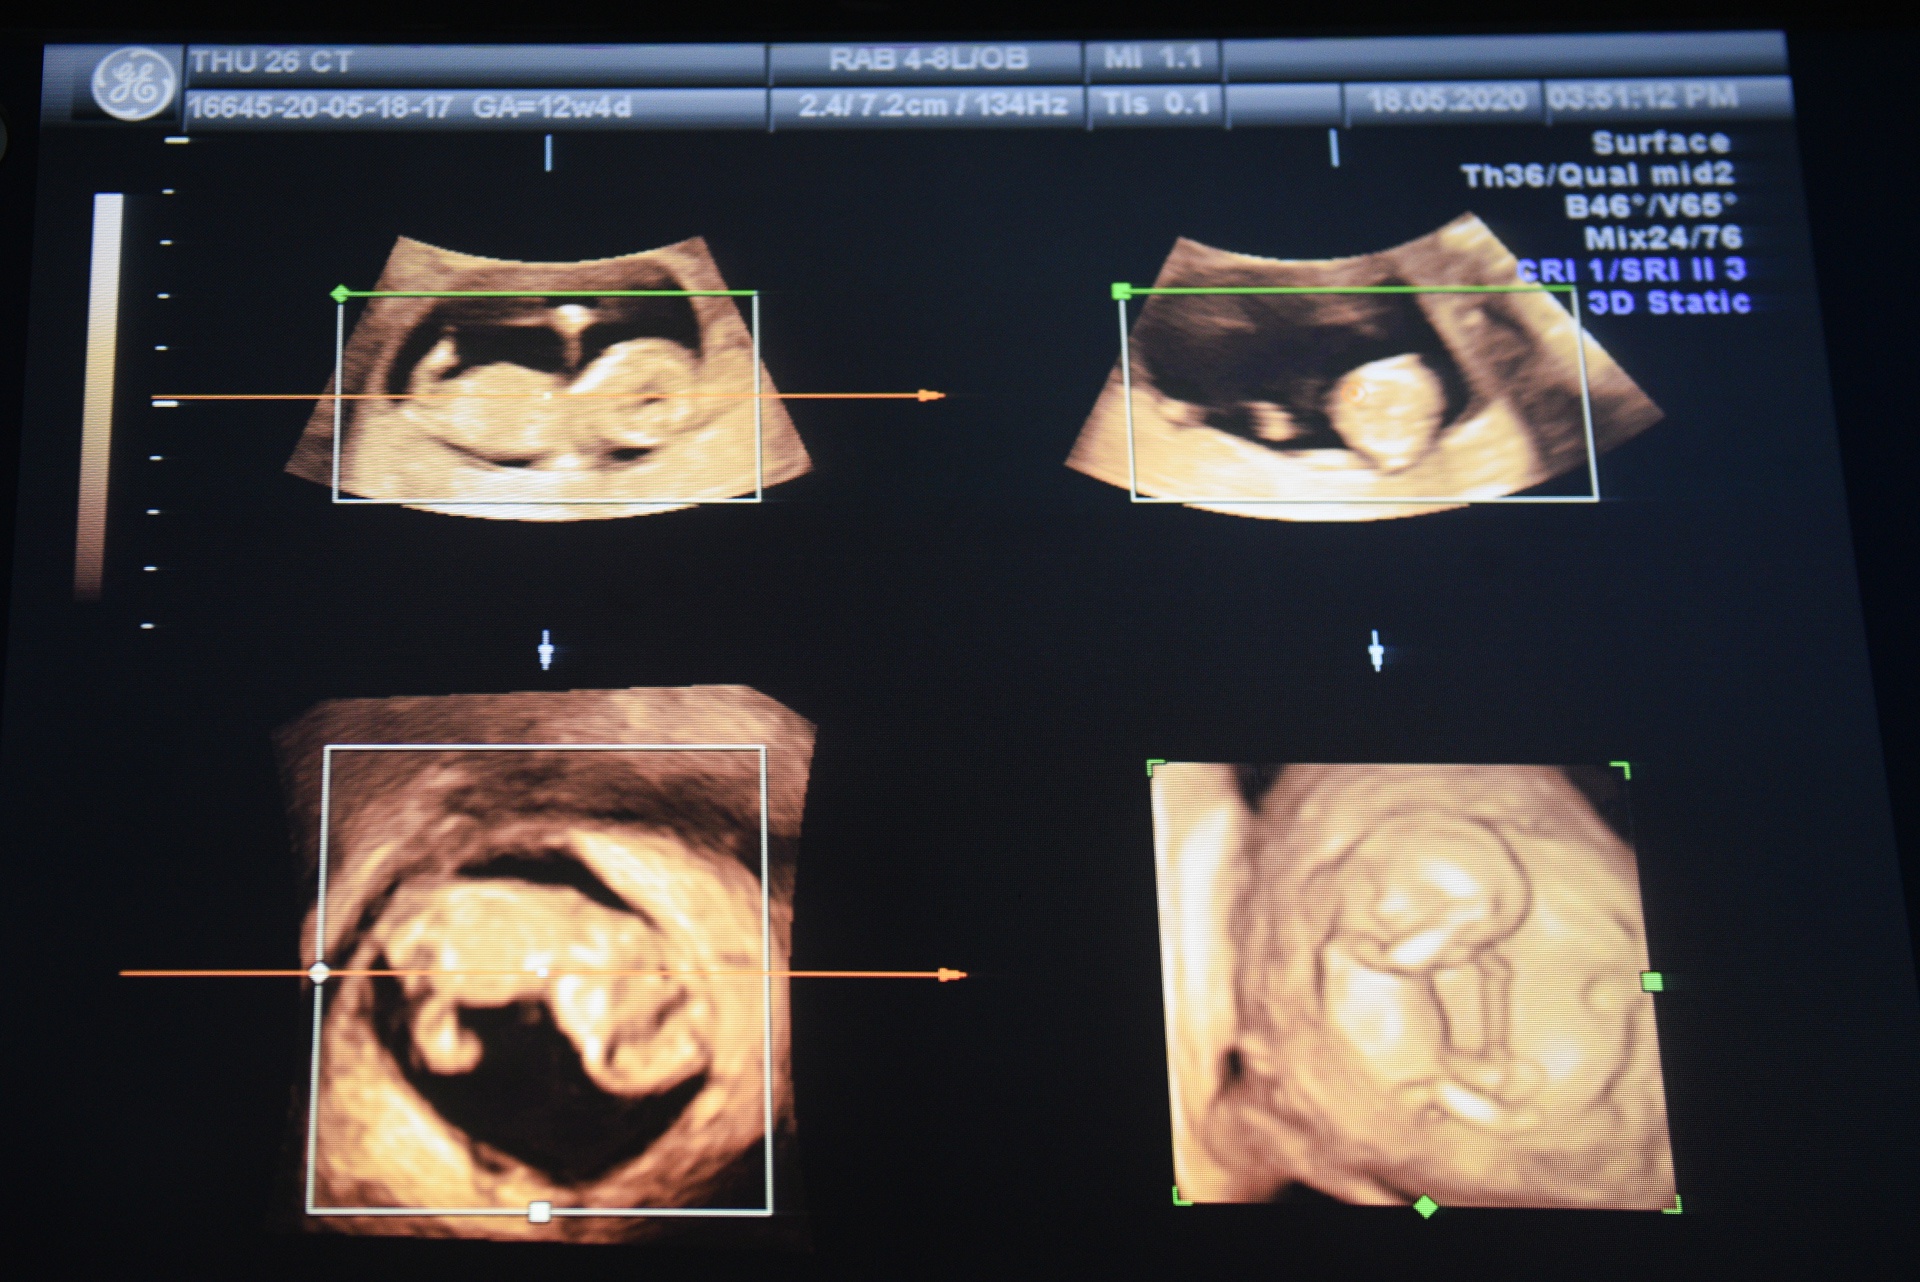

Bảo nghĩ ngay đến xin nghỉ việc ngày hôm sau để dành thời gian đưa Thu đi viện khám. Đó cũng là lần đầu tiên, anh nhìn thấy hình ảnh đứa con bé nhỏ hiện trên màn hình.

Bác sĩ nói em bé vừa nặng 10 gram. Nhưng bấy nhiêu thôi cũng đủ là món quà không gì sánh bằng mà Bảo và Thu nhận được.

Lần đi khám thai vừa rồi, bác sĩ nói em bé có chỉ số bình thường, phát triển đầy đủ. Chỉ nghe có vậy, đôi vợ chồng trẻ đều rơi nước mắt vì hạnh phúc.